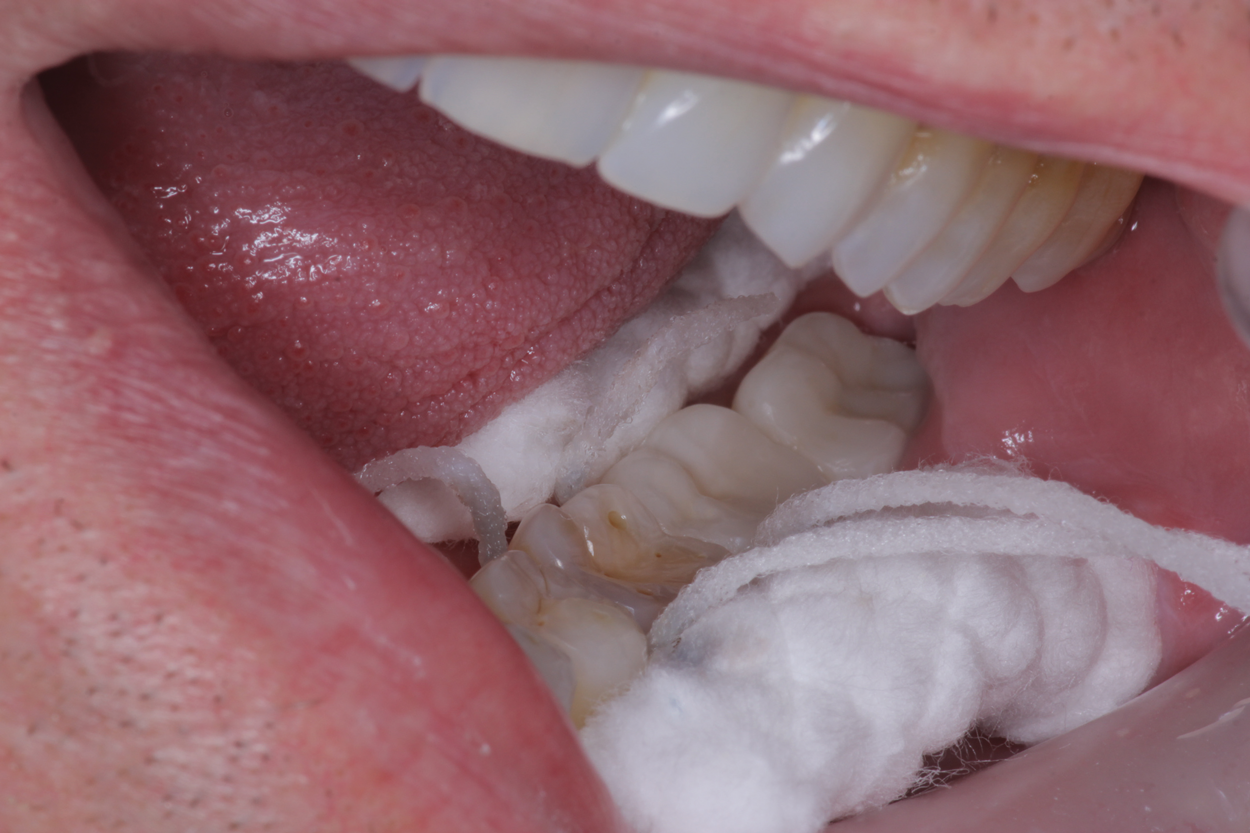

Another patient who benefited from SDF placement had recently been diagnosed with a large carious lesion. The patient was unable to complete treatment due to scheduling difficulties, but was experiencing substantial sensitivity. At one of her restorative appointments (for a different tooth), the doctor suggested SDF for the large carious lesion to arrest the decay and ease her sensitivity, explaining that she would likely need a second application for a more lasting effect. When she returned a few weeks later for her hygiene visit, she expressed concern that her sensitivity seemed to be returning. The doctor advised a second SDF application to be applied that day in the hygiene chair. The patient was also informed that a biannual placement of SDF would give her the best results until she was able to complete the restorative treatment. In this case, the patient left with zero sensitivity, and did not need to return for clinician chair time.